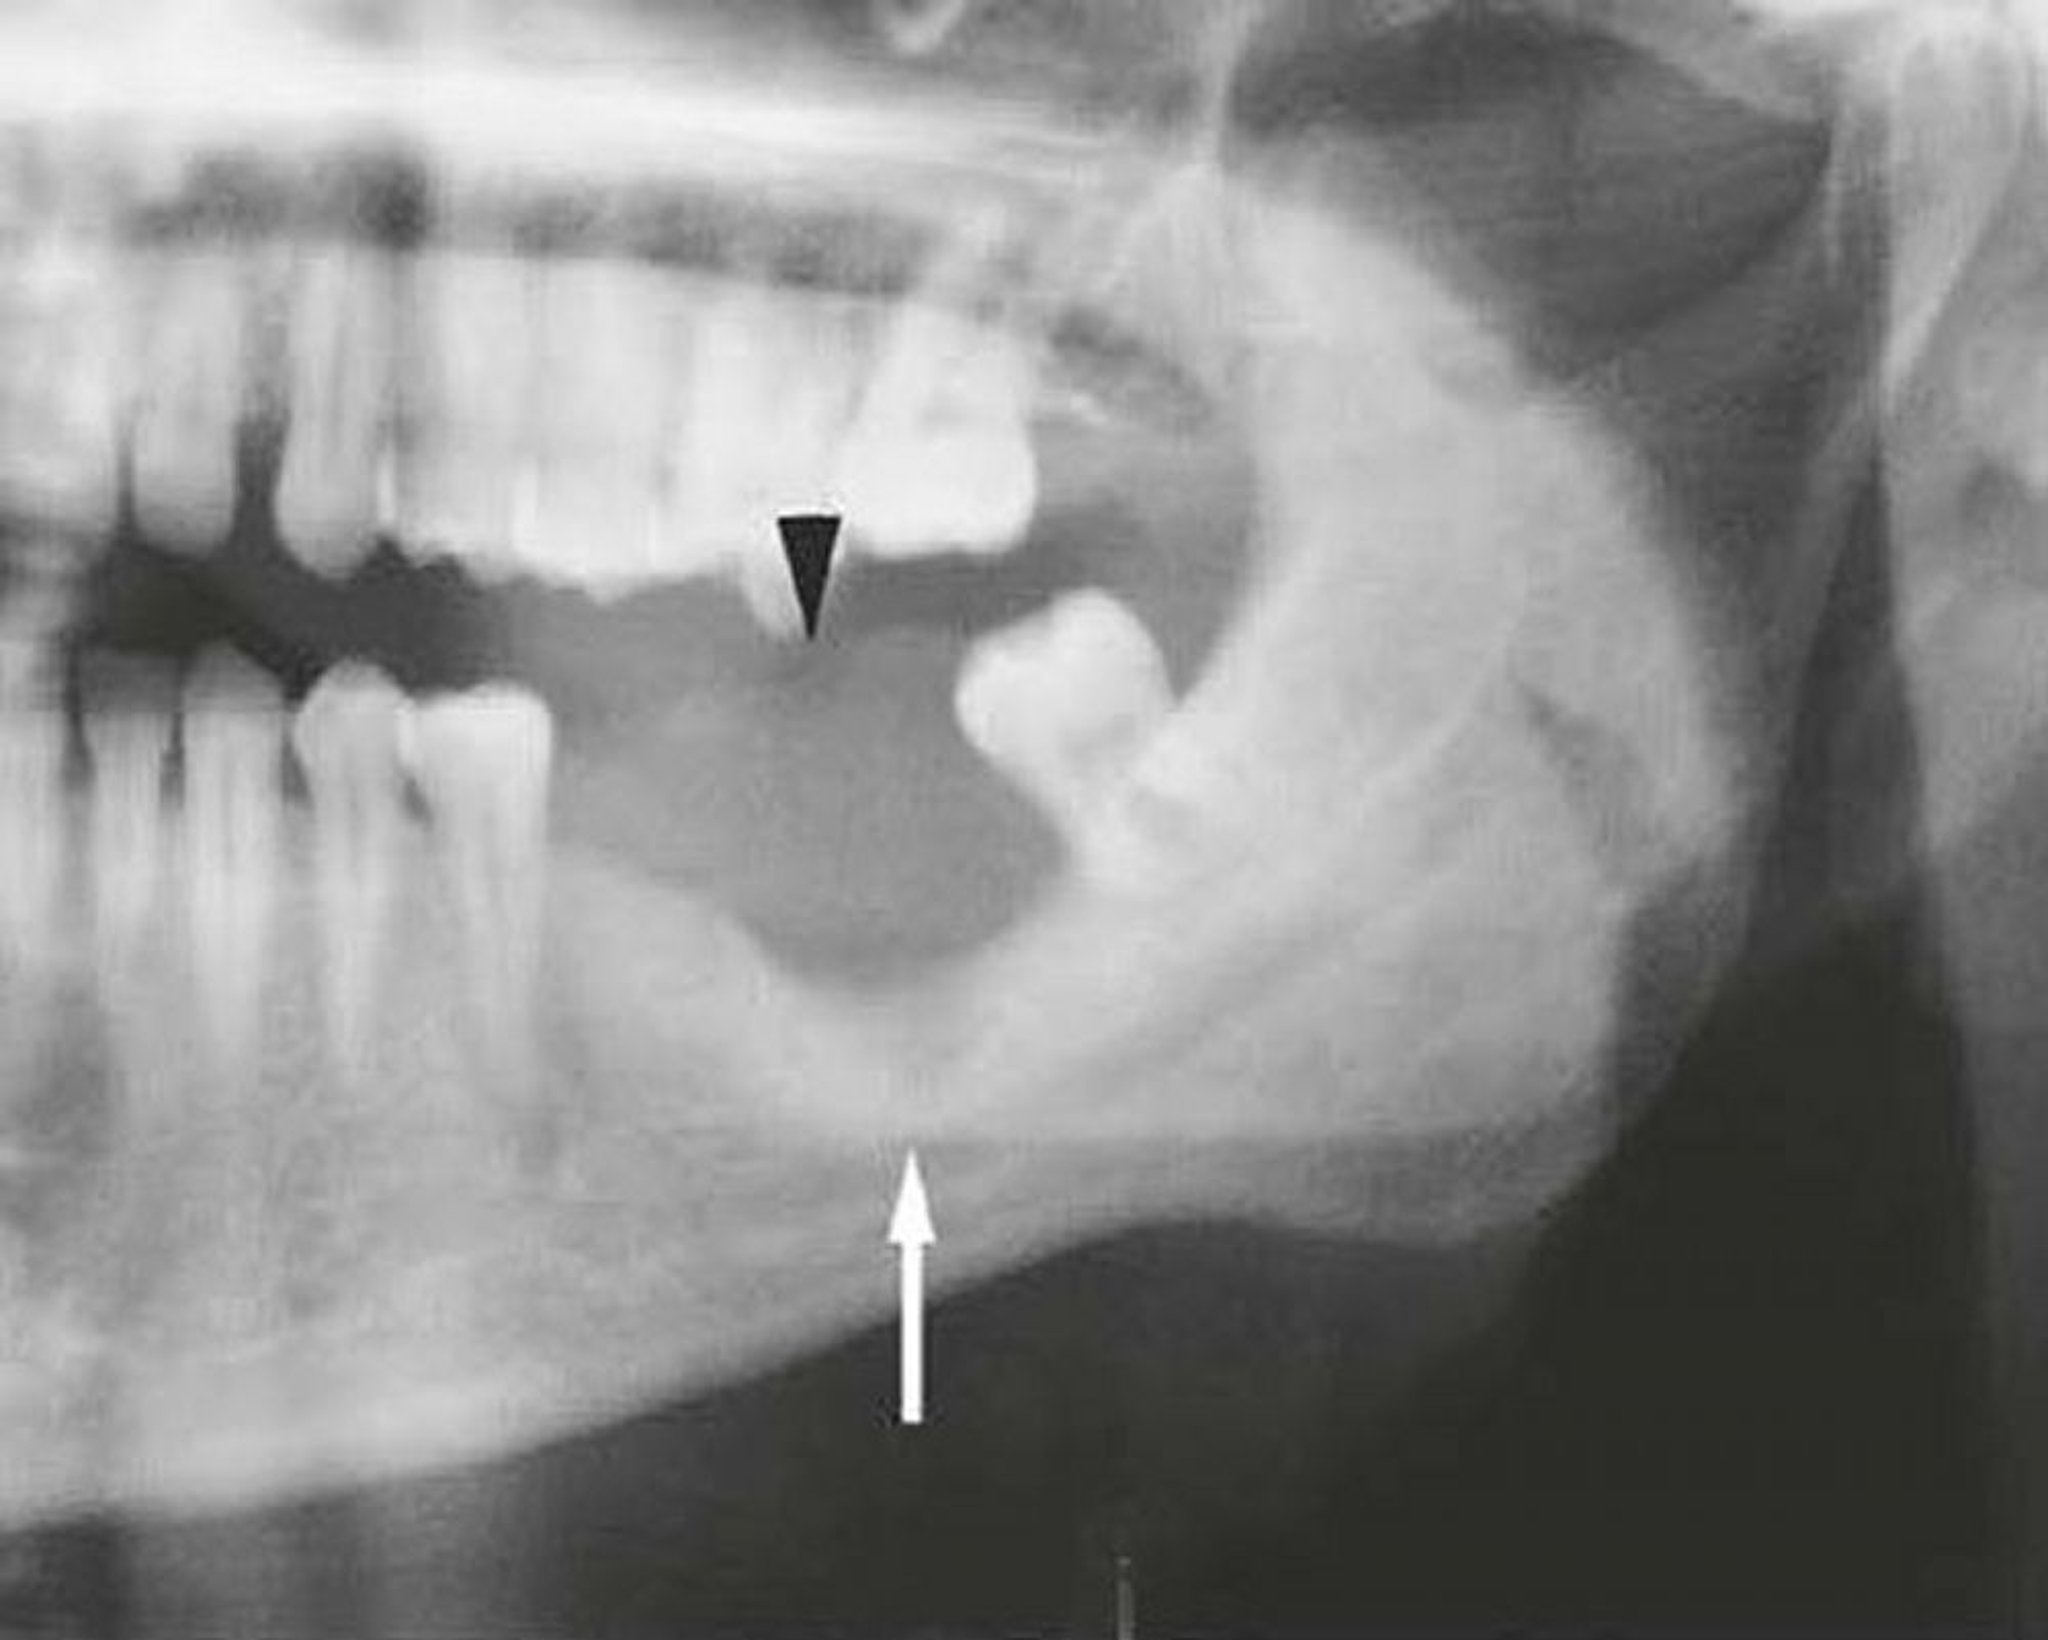

Carcinoma epidermoide de la mandíbula

Esta imagen de una mandíbula invadida por un carcinoma epidermoide muestra un tumor de partes blandas (punta de flecha) y destrucción ósea (flecha).